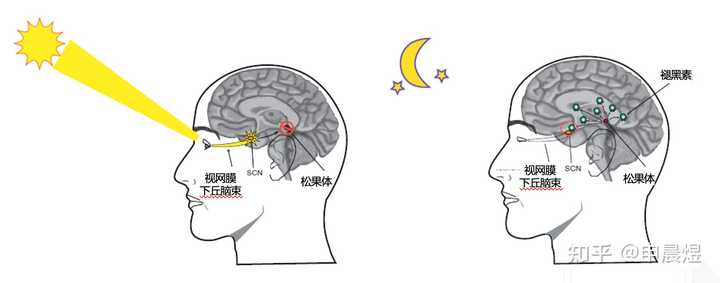

也称为“生物钟”,是机体内部发生的周期性变化过程,最典型的例子是睡眠与觉醒的周期性交替。昼夜节律(circadian rhythms) 是生物节律之一,是有机体在生物钟控制下产生的生物化学、生理学、行为模式的24h循环周期[1]。大多数生理和行为是由下丘脑生物钟控制的,分子钟作用于神经和内分泌通路,调节个体的生物节律,使机体在24h内适应外部环境的改变,并通过合成代谢和分解代谢来提高机体运转的效率[2]。

最新的研究也证实了,这三种细胞的也是日出而作日落而息,两点一线穿梭在血管和淋巴结之间。

图片摘要:The Sleep-Immune Crosstalk in Health and Disease。免疫细胞白天在血管里工作,晚上回到淋巴结里休息

如果熬夜工作熬夜运动,血液里的免疫细胞数量和活性不足,就会有更高的生病风险,同时也会影响淋巴结里免疫细胞适应性免疫反应的效率。

熬夜为什么会打乱免疫力?

说回熬夜和免疫力。最新的医学研究表明,熬夜可使T细胞及NK细胞的功能显著下降。通过对动物进行睡眠剥夺,发现动物体内一系列免疫指标发生变化,从而证明睡眠不足会增加感染风险。还有一些研究结果表明,睡眠对获得性免疫反应和免疫记忆的形成至关重要。